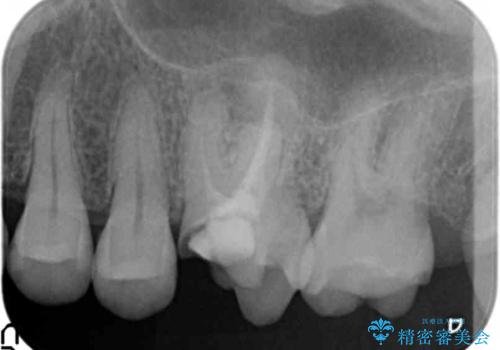

- 銀歯が取れたのち放置してしまいセラミック治療を希望され来院されました。

虫歯の再発も見られたので、丁寧に虫歯を取り除いたのち根管治療を行いジルコニアクラウン・セラミックインレーにより修復処置を行いました。